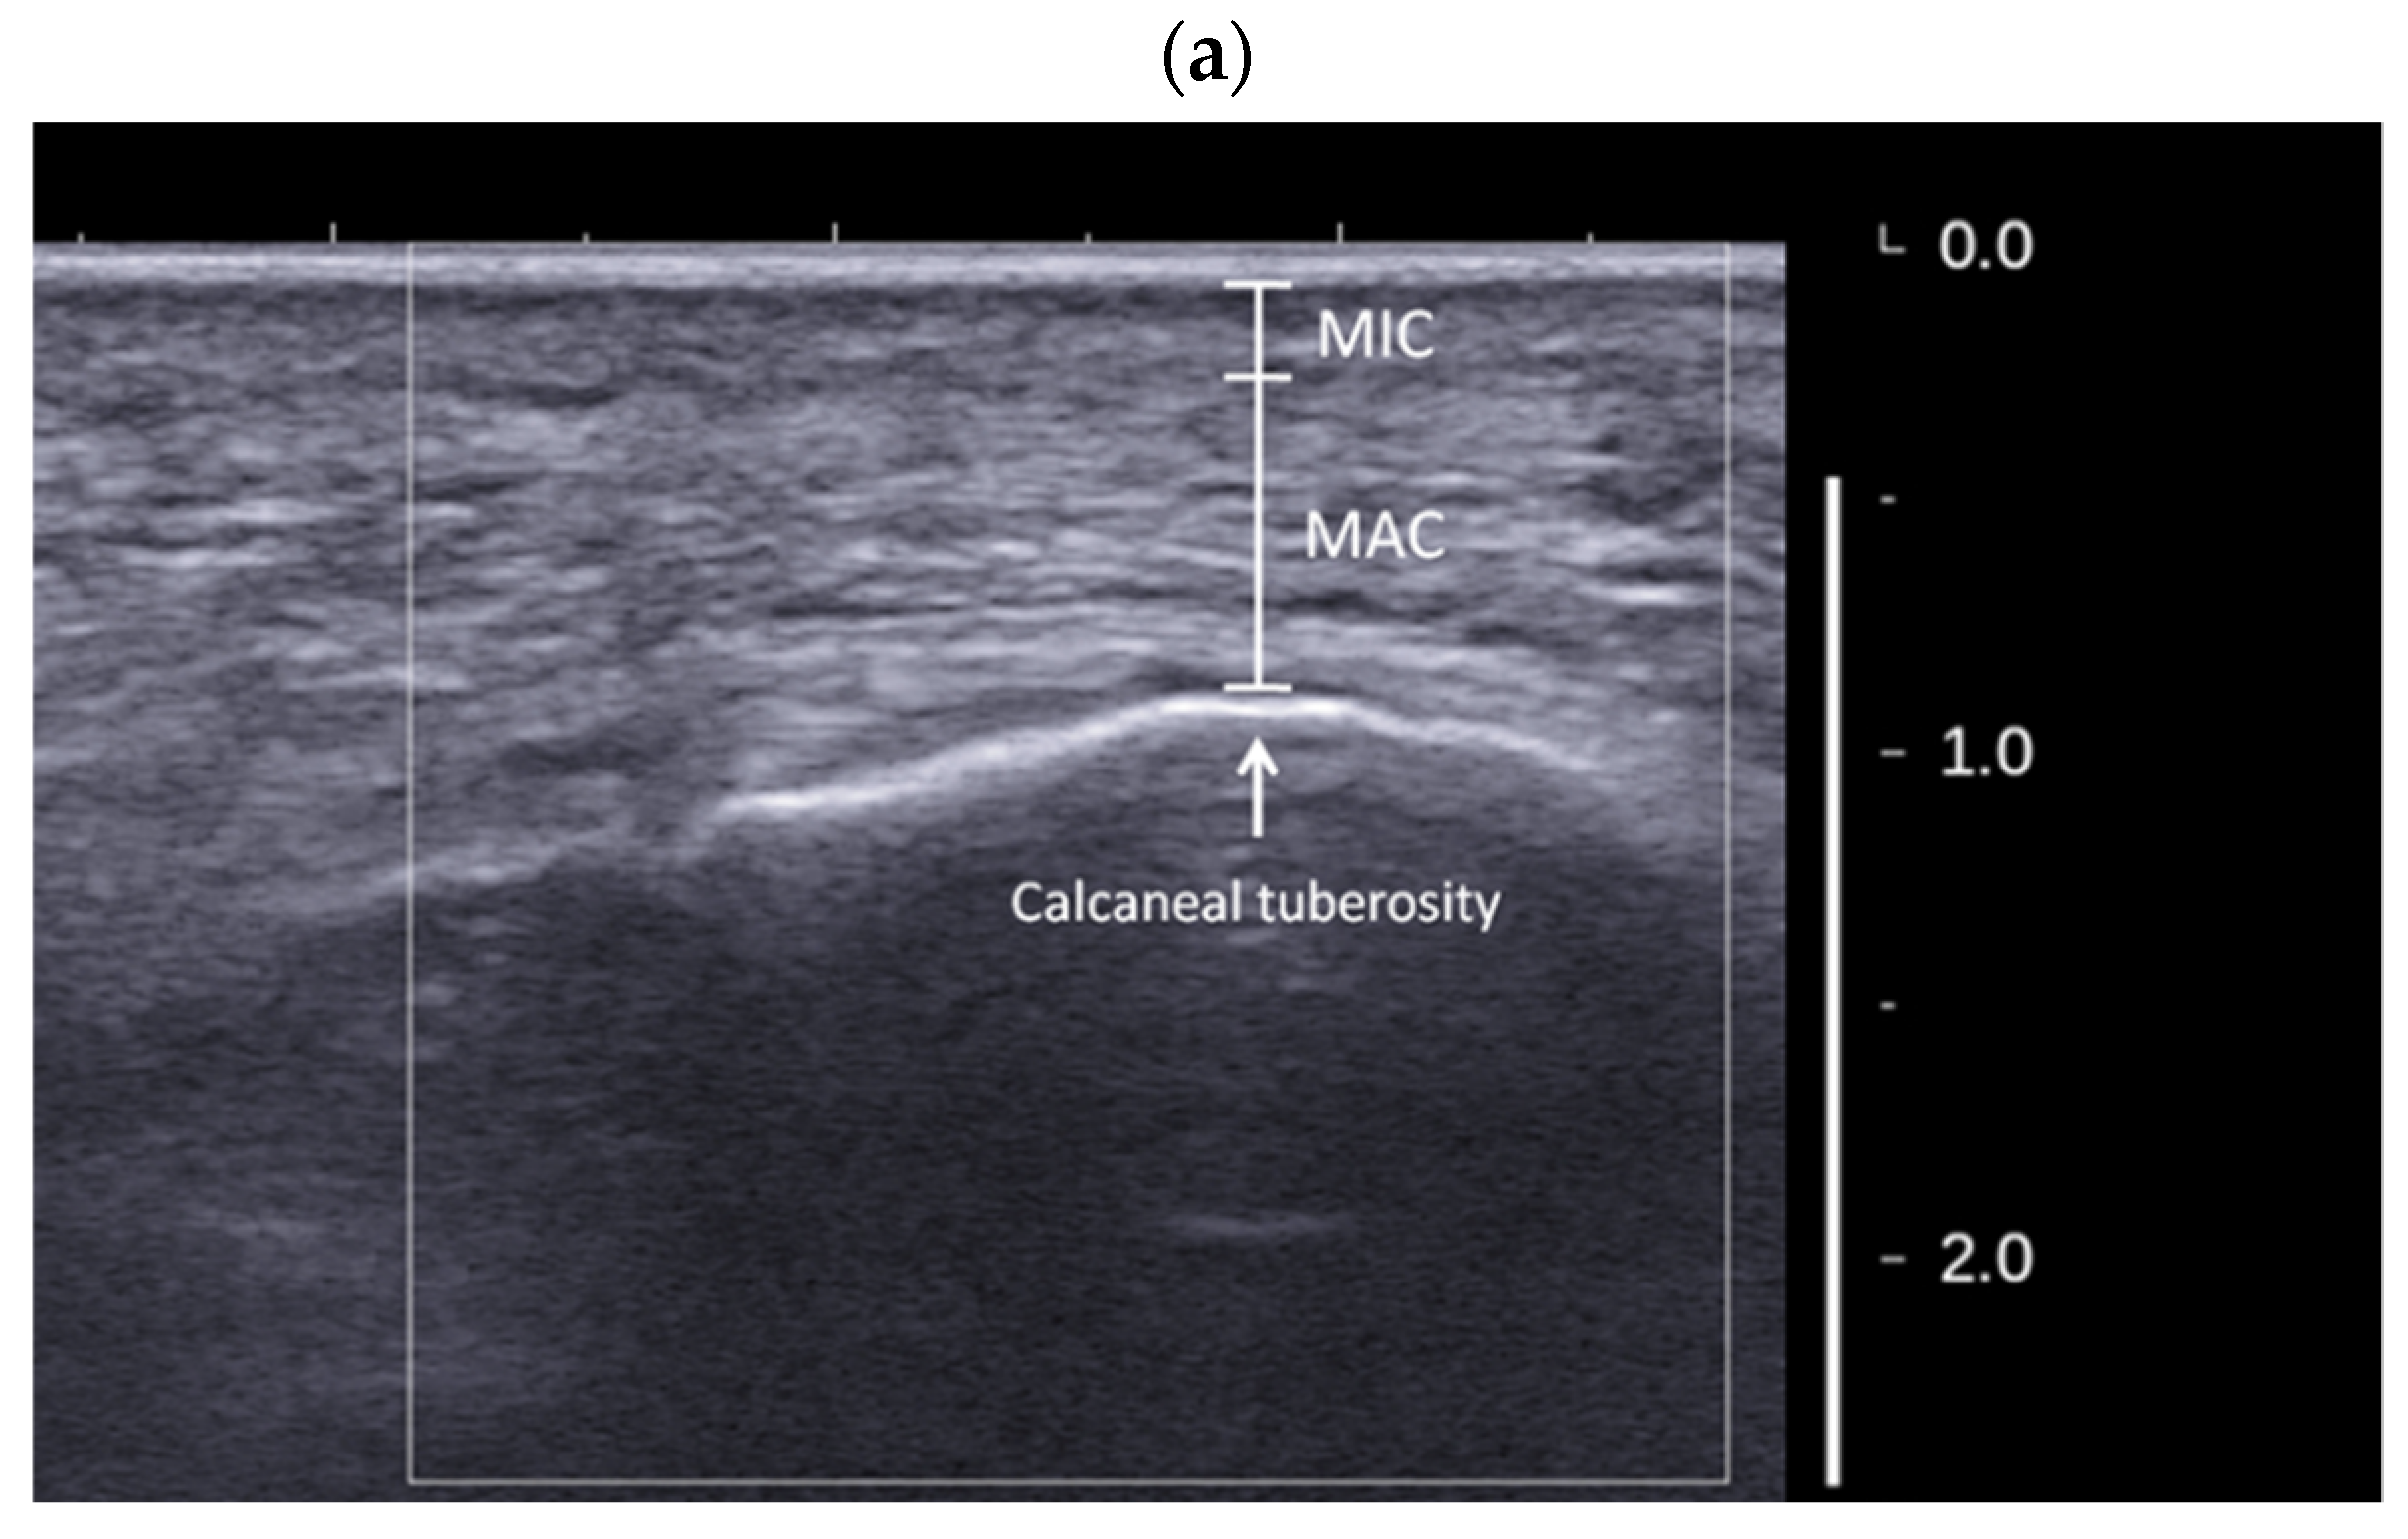

- Hsu, C.C.; Tsai, W.C.; Wang, C.L.; Pao, S.H.; Shau, Y.W.; Chuan, Y.S. Microchambers and macrochambers in heel pads: Are they functionally different? J. Appl. Physiol. 2007, 102, 2227–2231. [Google Scholar] [CrossRef]